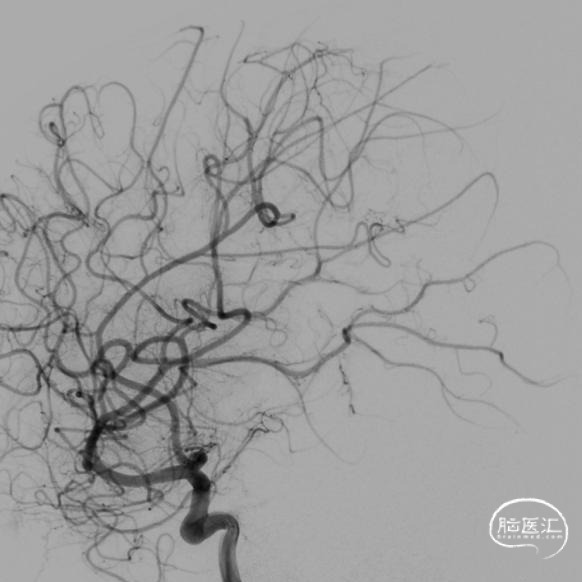

本例患儿肿瘤位于双侧额顶叶,大脑镰旁,增强扫描呈明显环形强化,提示肿瘤血运丰富。患儿年龄小,体重低,相对血容量少,如何控制术中出血是手术成功的关键。而术后肢体瘫痪或瘫痪加重是手术的主要并发症,中央沟静脉损伤、胼周动脉损伤、中央沟局部皮层损伤、癫痫、血肿以及脑水肿加重是其常见原因。术前脑血管造影有助于判断肿瘤与周围血管、组织的位置关系,明确上失状窦有无闭塞,对手术的切口设计有重要的参考价值及避免术中损伤不易发现的血管及组织。

本例患者术前脑血管造影提示瘤体主要由双侧大脑前动脉终末分支供血,造影静脉期瘤体显影明显,因此我们选择先采用神经介入技术超选部分主要供瘤动脉予弹簧圈栓塞,减少瘤体的供血。之后再行开颅探查双侧额顶叶占位性病变切除术。

儿童颅内肿瘤多血运丰富,且儿童本身体重低,血容量较少,开颅术中对于出血的控制尤为关键。术前尽可能的明确肿瘤与周围血管、组织间的关系,切口设计既要能够安全、彻底地切除肿瘤,又要避免无效开颅和无效脑暴露,增加不必要的医源性创伤,不可过分强调小骨窗,当肿瘤血运丰富,有条件时尽可能行供瘤血管栓塞,减少术中切肿瘤时出血。